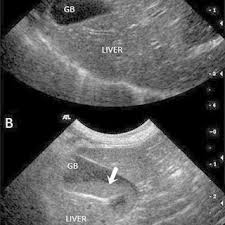

When seen signs include vomiting jaundice loss of appetite abdominal pain and fever. So after much research I want to share what Ive learned through my vet the ultrasound radiologist and the best medical sources of information on the Internet about gallstones gallbladder and bile duct inflammation in cats.